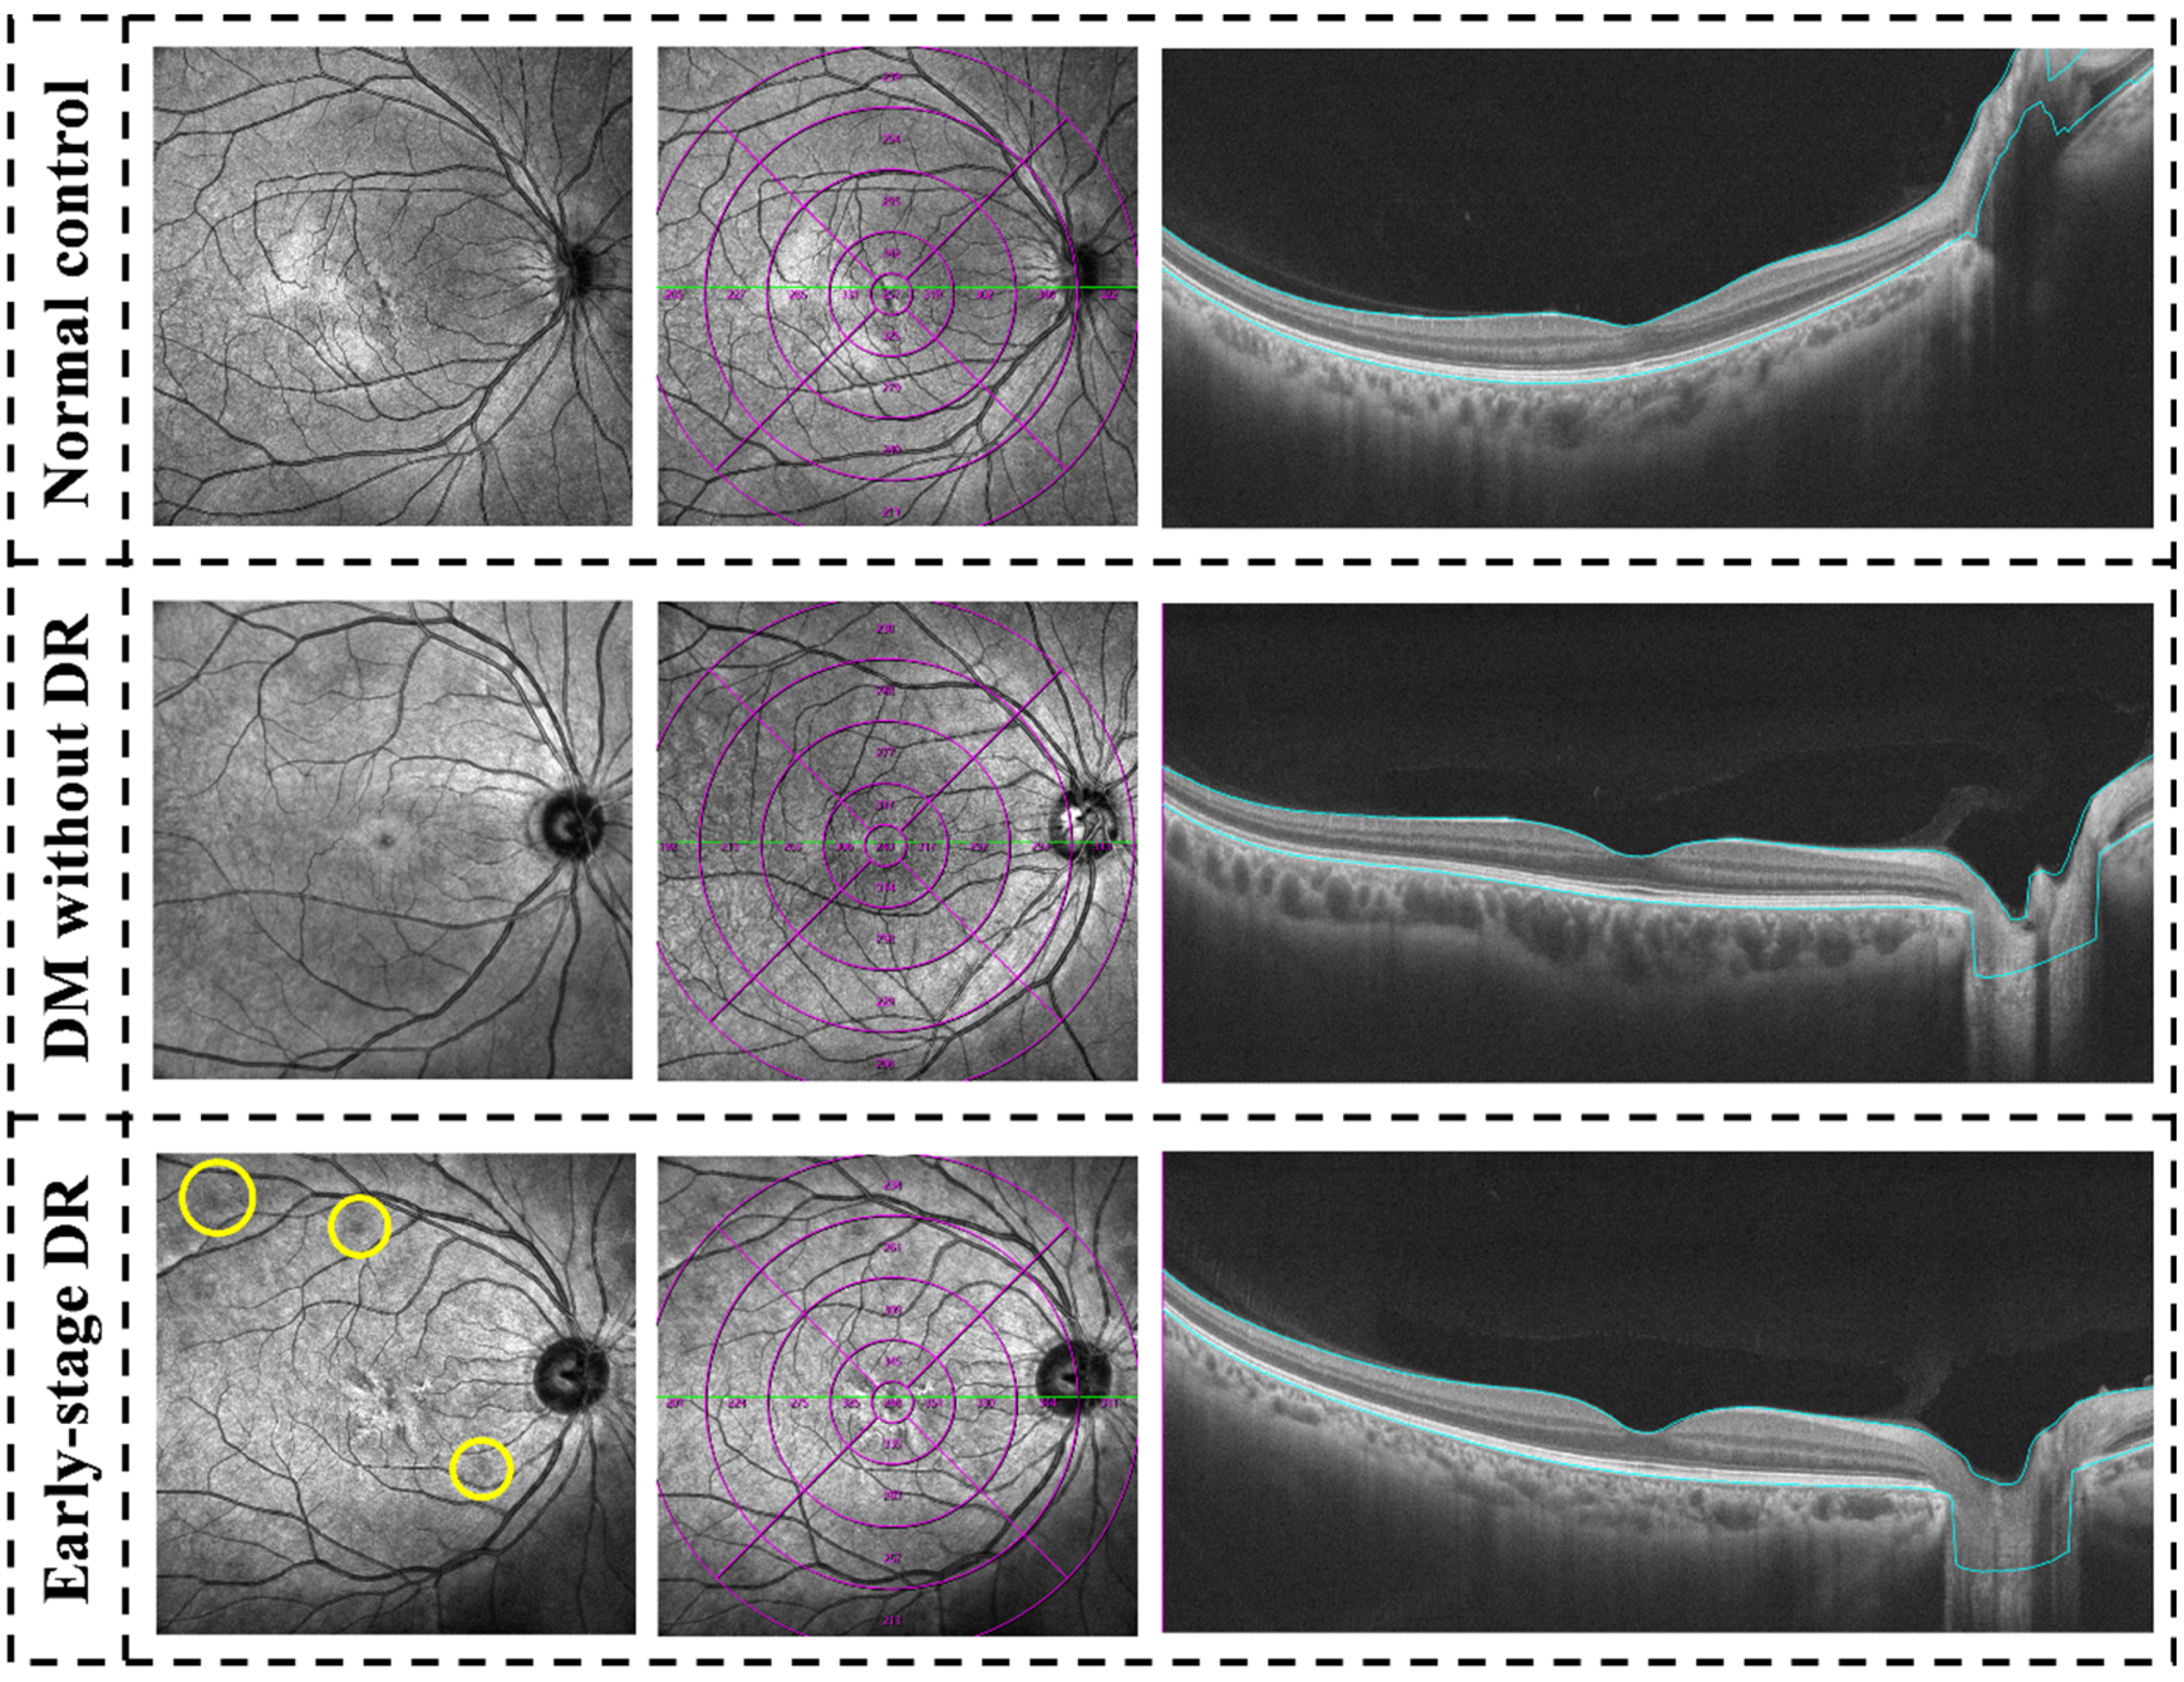

2.2. Ophthalmic Examinations and Blood Test

5.2. Quantitative Evaluation of the Inner Retina

5.3. Quantitative Evaluation of SCP

5.4. Quantitative Evaluation of DCP

5.5. Quantitative Evaluation of CMT

5.6. Qualitative Evaluation of the Concentric Ring Area